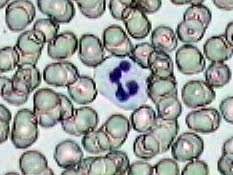

Imágenes tomadas de las preparaciones de los alumnos de 3º ESO sobre un frotis sanguíneo